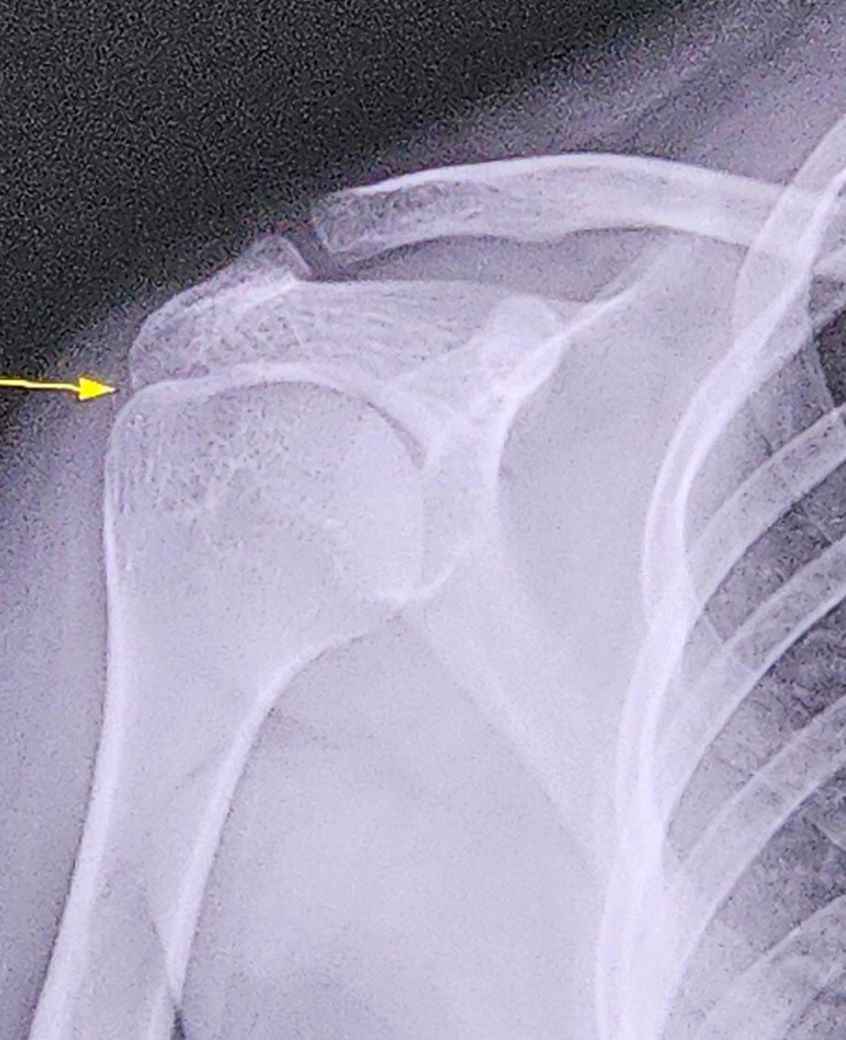

제가 4월 18일 날 어깨관절의 염좌 및 긴장[우측] 질환을 받았습니다 그때 배드민턴을 하다가 어깨가 꺾여서 갔어요 배드민턴 금지령을 받고 조금 쉬다가 했는데 꺾일뻔한 사건이 많았는데 아 진짜 조심히 했는데 또 꺾였어요... 똑같은 부위인것 같은데.. 어쩌죠.. 오늘 한번은 글씨를 잘 쓰다가 갑자기 손이 덜덜 떨려서 겨우 썼고요 사진은 4월 18일날 엑스레이 사진 입니다 견봉하공간이 아예 없어요 어깨가 붙어버려서 다시 떨어질수도(원래 상태로 돌아갈수 있는건가요?) 있는건가요..? 병원 가면 아예 배드민턴 하지 말라고 할 것 같은데... 제가 11월 4일날 정형외과 가서.. 중족골통(좌측] 근근막통증후군, 아래다리[좌측] 진단 받아서.. 이것도 배드민턴 때문에 아이 그래도 배드민턴은 포기 못하는데.. 어깨 이제 못쓰면 사격도 못하는데.. 병원 안가면 안되겠죠..?

견봉하 공간이 좁다면 "충돌증후군이나 염증 재발"로 관절이 붙은 듯한 느낌이 생길 수 있습니다.